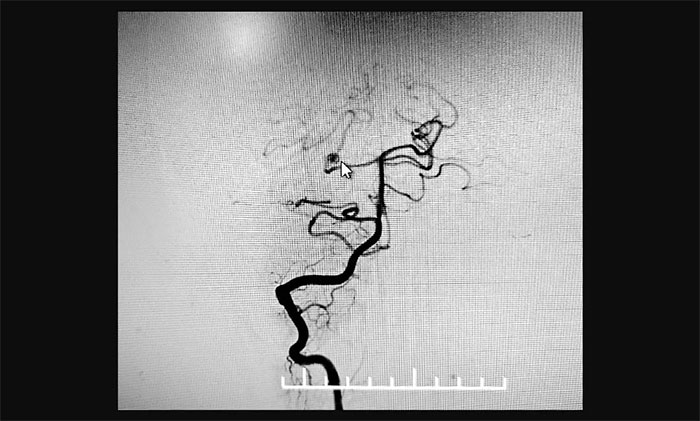

最终,在麻醉科团队及导管室介入团队的密切配合和监护下,神经外科于耀宇主任团队历时2小时,为王女士顺利实施脑血管造影+颅内动脉瘤栓塞术。术中,DSA造影确诊右侧小脑上动脉夹层动脉瘤,动脉瘤瘤体大小约为4x3 mm。术中,于耀宇主任凭借娴熟的技术,克服血管迂曲等困难,将栓塞导管成功送入夹层动脉瘤内,最终顺利栓塞夹层动脉瘤。术后,再次造影未见动脉瘤显影,见远端分支显影良好,“炸弹”危险被成功解除。术后,患者顺利苏醒,无神经功能障碍。

▲ 栓塞后